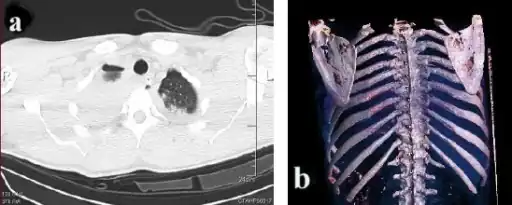

A right sided scapula fracture with rib fractures underneath seen on a 3D reconstruction of a CT scan